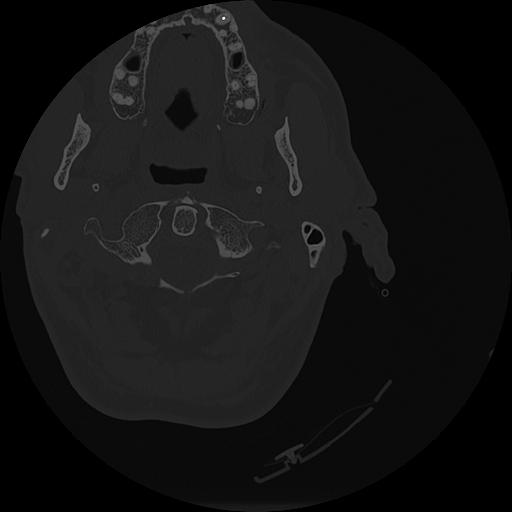

7 HUESO,,Vol,0.5,HUESO,,